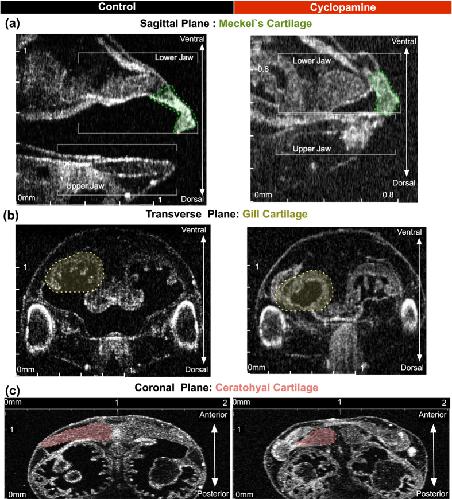

Figure 3. Imaging Xenopus craniofacial structures with OCT (a) We create a slit at the center of the clay with the Stage 46 tadpole positioned ventrally towards the OCT imaging plane (XZ-plane). Then we adjust the 5-axis stage to capture a zero- degree reference axis where a plane intersects the tadpoleâs eyes symmetrically and the tip of the tail. This plane defines the 0° orthogonal plane. We then move this imaging plane in y, x and z axes to capture transverse, sagittal and coronal sections respectively. Imaging planes are adjusted on all three axes to capture distinct facial structures. (b) Top panel shows the schematic representation of the three neural crest streams: mandibular (green), hyoid (pink) and branchial (yellow) which form Meckel, ceratohyal and gill cartilages respectively. Each structure is highlighted under simple stereomicroscopy image (middle panel) and after alcian blue stain (bottom panel) (c) OCT images of craniofacial structures in all three planes: Transverse, Sagittal and Coronal. Meckelâs cartilage (green label) is best viewed in sagittal (yz-axis) and coronal (xy-axis) sections. The ceratohyalcartilage can be easily resolved by the coronal sections. The gill cartilages are more posterior compared to Meckelâs and ceratohyalcartilage, and the gill cartilages occupies most of the craniofacial space. Qualitative analyses can be made in all axes.

Figure 4. Qualitative neural crest defects in Xenopus with cyclopamine treatment.Stage 46 uninjected control tadpole compared to cyclopamine treated tadpoles and demonstrated the teratogenic effects. (aâc) Left column shows the control and the right column shows the cyclopamine treated tadpole. In cyclopamine treated tadpoles both jaws were short and thick. Meckel and ceratohyalcartilage were smaller and gill cartilages were nearly lost. (Scale Bar on x and y axis: 0â2âmm).